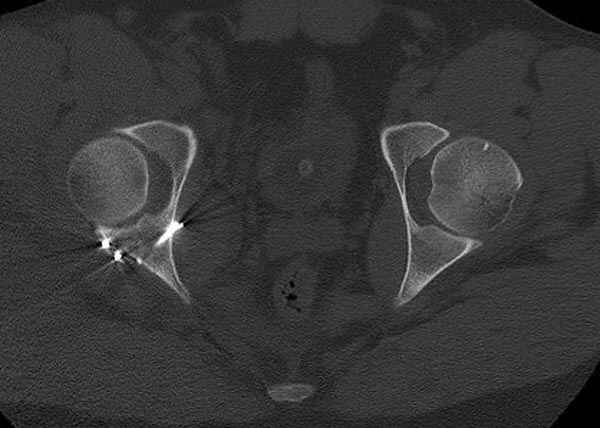

11:50 больной в послеоперационной, рентгенограмма N7, компьютерная томограмма в тот же день N8-10